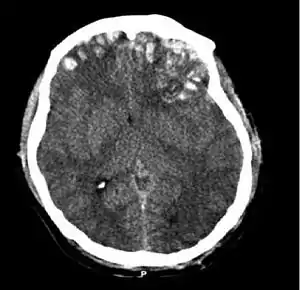

![]() КТ-сканування, на якому видно забиття мозку, геморагію у його півкулях, субдуральну гематому та перелом черепа КТ-сканування, на якому видно забиття мозку, геморагію у його півкулях, субдуральну гематому та перелом черепа | |